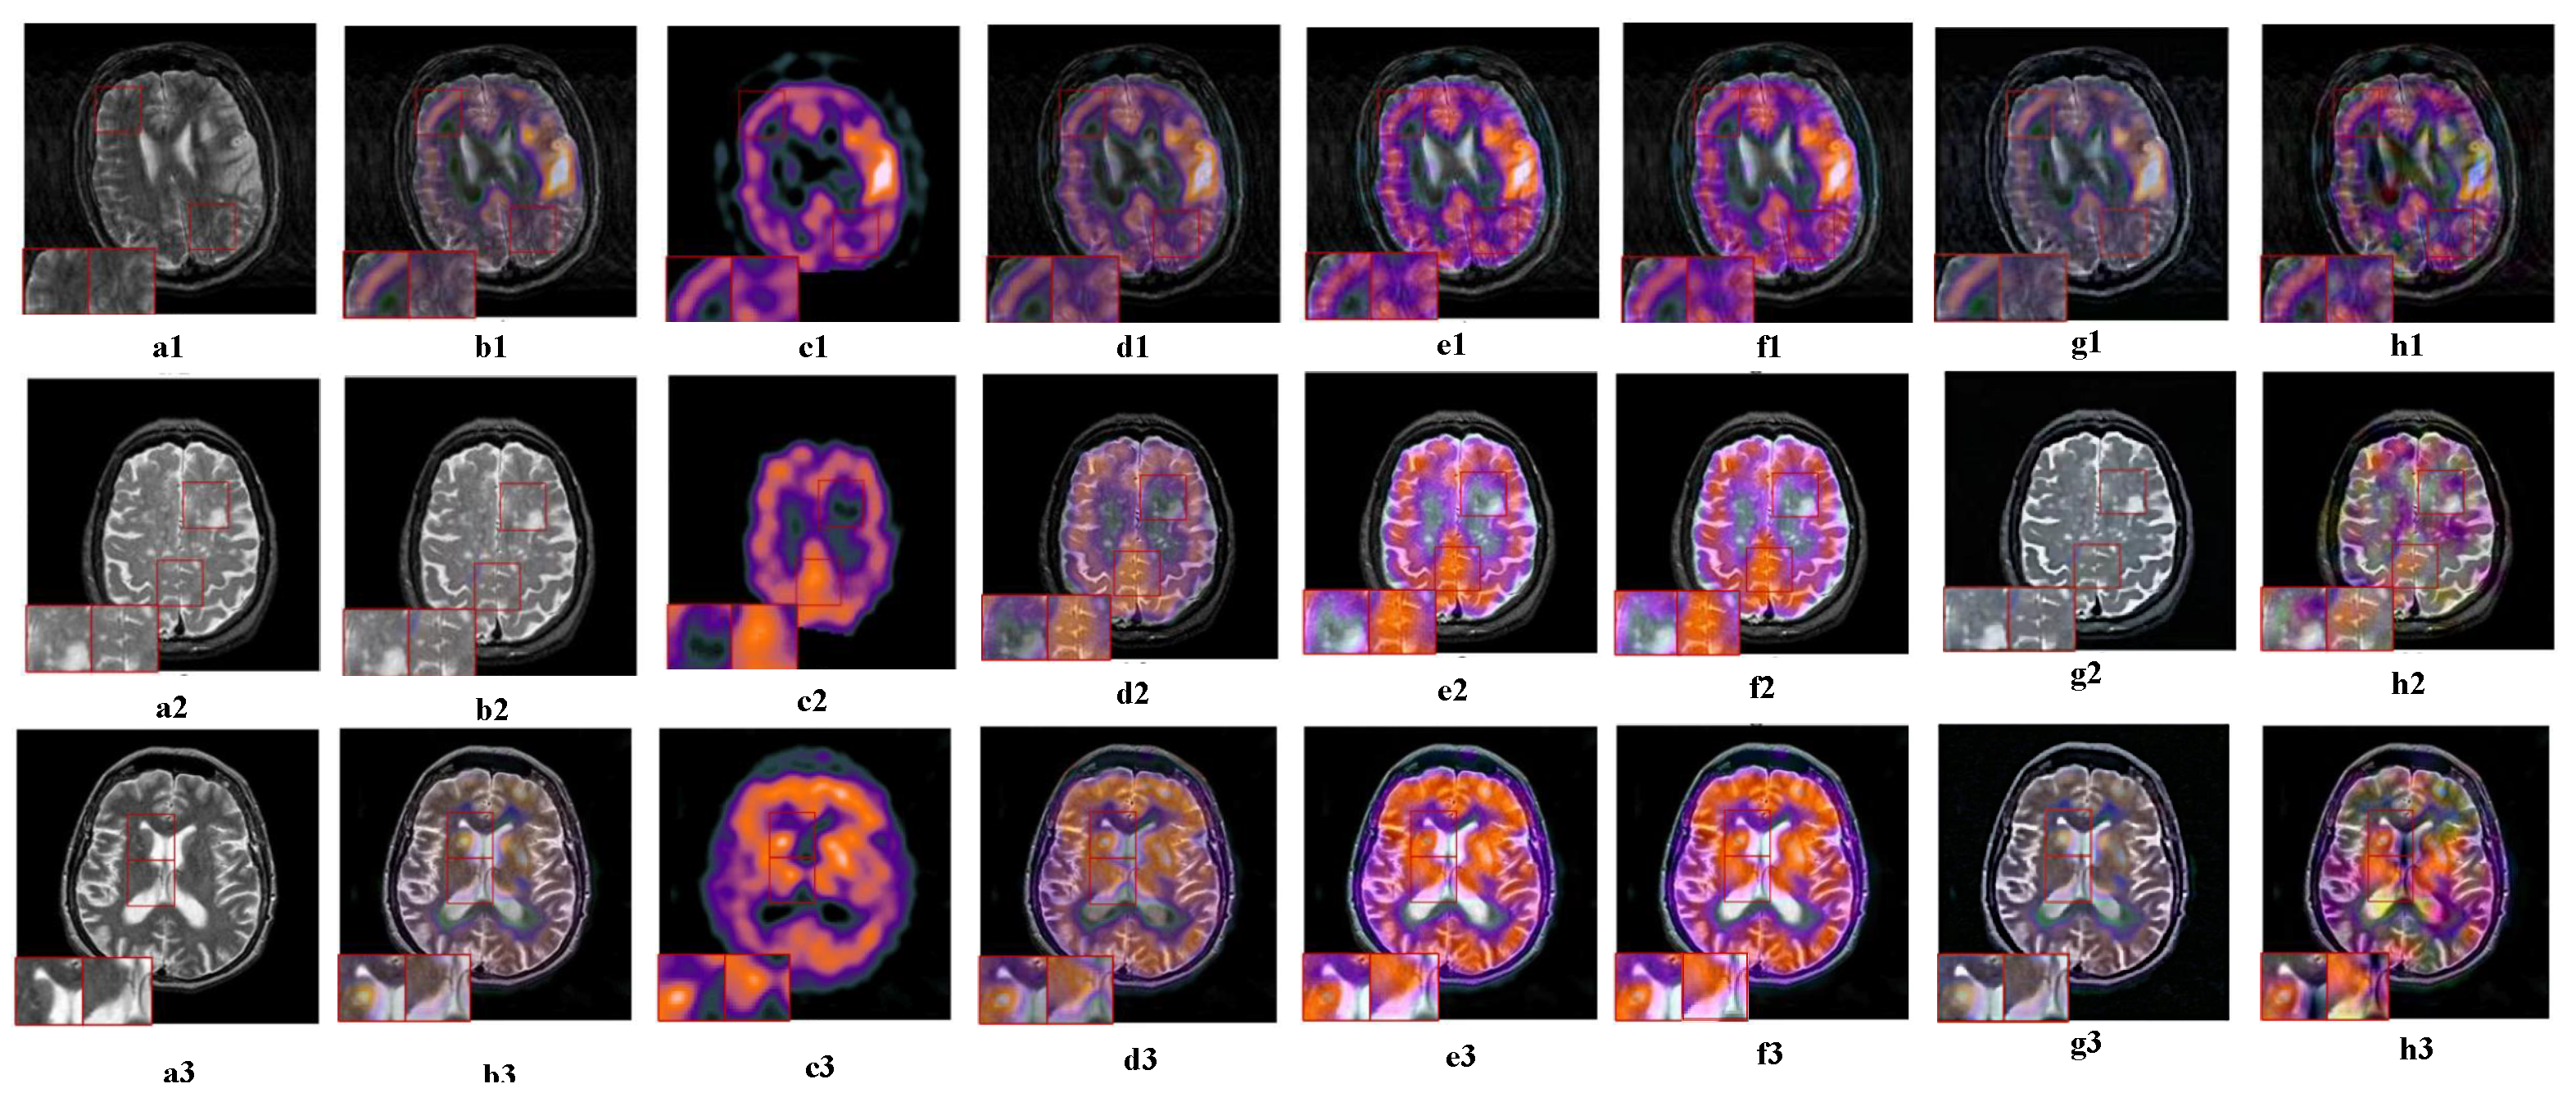

5.2.4. Fusion Analysis on MRI-PET

5.2.5. Fusion Analysis on MR-SPECT

5.3. Objective Metrics Analysis